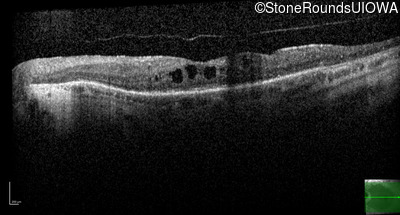

AR Retinitis Pigmentosa (IA1aiii)

Age at visit: 46 years

This 46 year old man has had poor vision in dim light since age 2.

Diagnosis & molecular findings

AR Retinitis Pigmentosa SLC24A1 Met252 del2ggaAT Leu1052 del2ctTC AR